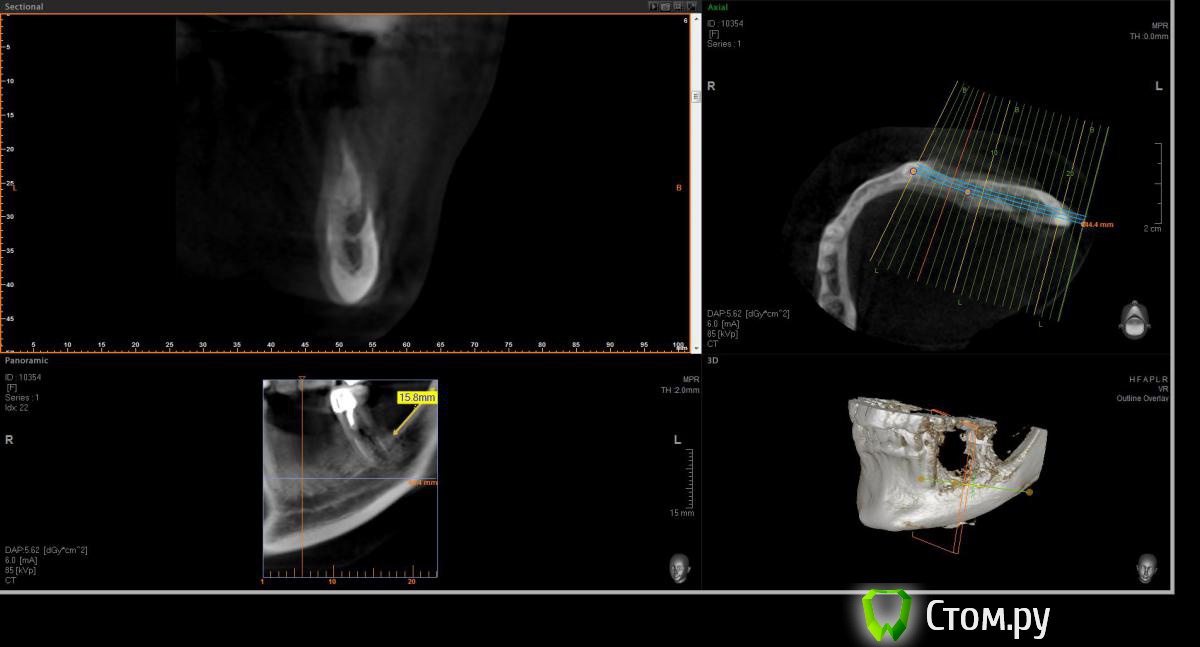

Opimar Опубликовано 21 июня, 2014 Поделиться Опубликовано 21 июня, 2014 Здравствуйте коллеги. Прошу вашей помощи и совета с пациенктой. В анамнезе травматичное удаление около 2-3 лет назад 35-36. Со слов пацинтки удалялось долотом и в 2 приема, вообщем по прошествию времени результат плачевный К мостовидному протезу пациентка не готова, очень хочет лечение с имплантантами и готова к костной пластике. Восстановить такой дефект ,если я правильно понимаю, более-менее прогнозируемо можно только с трансплантацией аутокостных блоков. Как раз по типу того как выкладывал Mane http://forum.stom.ru/topic/25799-kk-monokortikalnye-bloki/ либо по Кюри. Сам склоняюсь к забору блока с наружной косой линии или с подбородка. С блоками работать буду первый раз. Прослушал курсы Томаса Хансера. Прошу высазать идеи и предложения,возможны ли альтернативные методы? Кт прилагаю. Спасибо Ссылка на комментарий

Opimar Опубликовано 21 июня, 2014 Автор Поделиться Опубликовано 21 июня, 2014 Выкладываю еще. Пошагово от 34-37 Ссылка на комментарий

Bier Опубликовано 21 июня, 2014 Поделиться Опубликовано 21 июня, 2014 Выкладываю еще. Пошагово от 34-37темная точка достаточно высоко, это по моему не нерв, нерв ниже, я правильно понимаю? Ссылка на комментарий

Opimar Опубликовано 21 июня, 2014 Автор Поделиться Опубликовано 21 июня, 2014 темная точка достаточно высоко, это по моему не нерв, нерв ниже, я правильно понимаю?Да он ниже и язычнее. Провел от менталиса там еще запас есть. Ссылка на комментарий